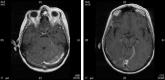

VZV Meningoencephalitis